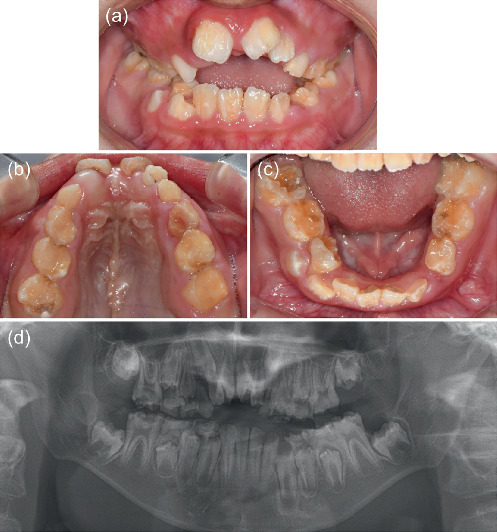

梅干腹综合征(PBS)是一种罕见的先天性疾病,以腹壁肌肉发育不全、泌尿系统异常和双侧隐睾为特征。本报告描述了一例罕见的PBS患者的畸形发育不全。病例介绍:一名患有PBS的10岁男孩,表现为言语和咀嚼困难。口腔及影像学检查显示异常发育不全的牙釉质缺损、下颌发育不全及后缩、上颌缩窄及前牙开咬。结论:虽然PBS的牙齿表现并不常见,但罕见的病例可能会出现异常的发育不全。

Introduction: Prune belly syndrome (PBS) is a rare congenital disease characterized by hypoplastic abdominal wall muscles, urological abnormalities, and bilateral cryptorchidism. This report describes a rare case of aberrant hypoplastic amelogenesis imperfecta in a patient with PBS. Case Presentation: A 10-year-old boy with PBS presented with difficulties in speech and mastication. Oral and radiological examinations revealed aberrant hypoplastic enamel defects, mandibular hypoplasia and retrusion, maxillary constriction, and anterior open bite. Conclusion: Although dental manifestations are not frequent in PBS, rare cases may present with aberrant hypoplastic amelogenesis imperfecta.